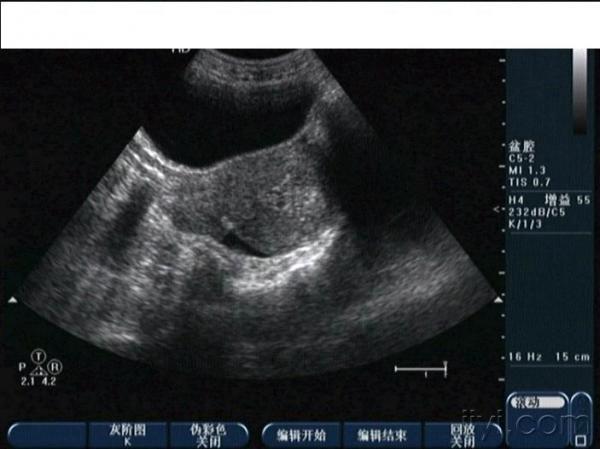

子宫穿孔超声表现图

子宫穿孔超声表现图,子宫穿孔超声图片

超声典型病例子宫穿孔

超声诊断子宫穿孔并大网膜嵌顿1例

子宫穿孔彩超下表现

子宫穿孔彩超图

子宫穿孔b超图片

子宫穿孔b超报告图片